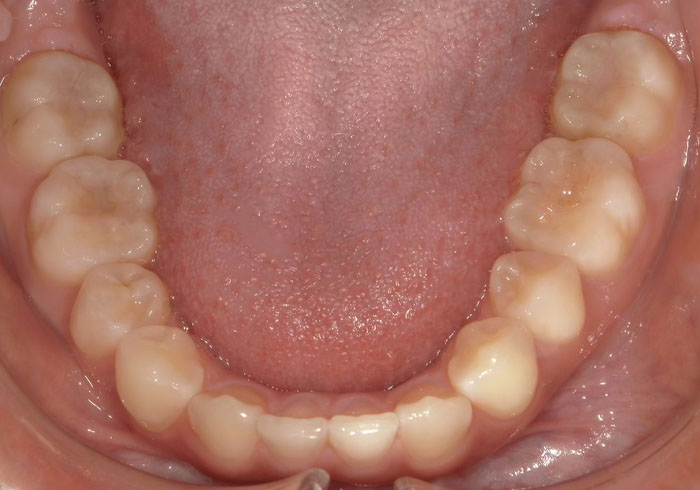

口腔内写真

治療前

マウスピース矯正 マウスピース矯正 マウスピース矯正